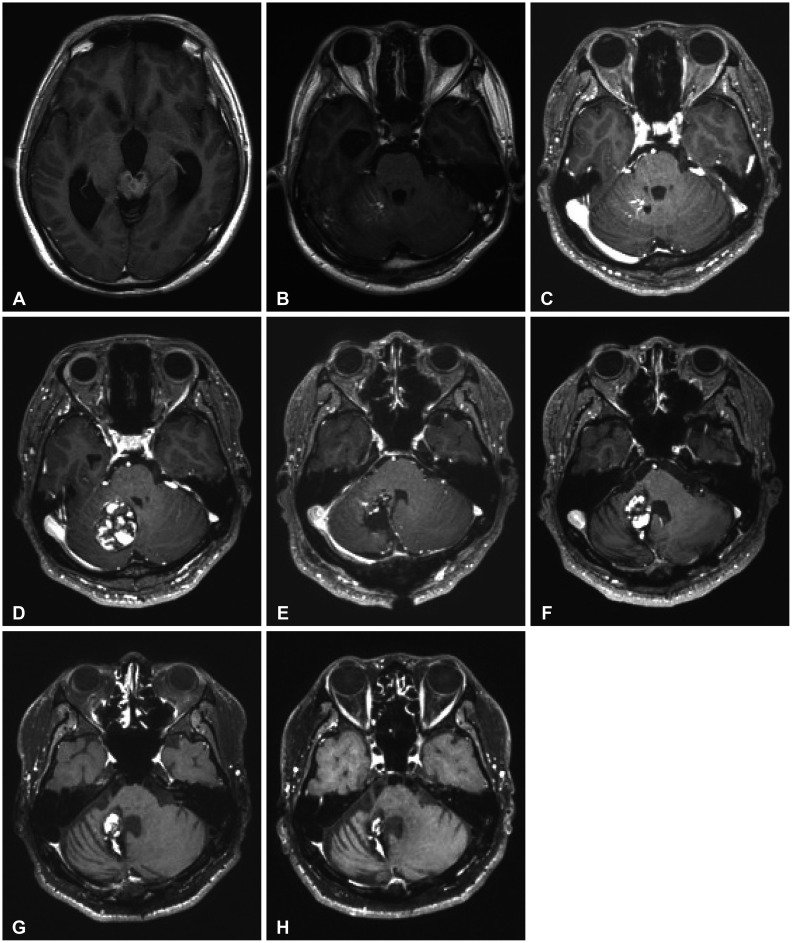

辐射诱发海绵体畸形(RICMs)是高剂量放射治疗的罕见但重要的晚期并发症,特别是在年轻的脑肿瘤幸存者中。本报告报告了两例经积极多模式治疗的RICMs,包括手术、化疗和放疗。病例1是一名22岁男性髓母细胞瘤患者,接受颅脊髓照射、肿瘤床增强和串联自体外周血干细胞移植治疗。治疗完成约8年后,常规随访影像学显示右侧小脑局灶性小出血,符合RICM。该病变无症状,采用常规影像学保守治疗,随着时间的推移显示自发消退,治疗后9年显著缩小。病例2描述了一名32岁男性颅内生殖细胞瘤接受全心室照射治疗。治疗三年后,患者在已存在的发育性静脉异常附近出现了症状性出血性RICM。手术切除和伽玛刀手术稳定病变;然而,残余症状,包括震颤和步态障碍,持续存在,影响患者的日常活动。这些病例说明了RICMs的不同临床过程,从自发消退到手术干预的必要性,并强调了长期监测和针对晚发性并发症的量身定制管理策略的重要性。

Radiation-induced cavernous malformations (RICMs) are rare but significant late complications of high-dose radiation therapy, particularly in young survivors of brain tumors. This report presents two cases of RICMs following aggressive multimodal treatment, including surgery, chemotherapy, and radiation therapy. Case 1 was a 22-year-old male patient with medulloblastoma treated with craniospinal irradiation, tumor bed boost, and tandem autologous peripheral blood stem cell transplantation. Approximately 8 years after treatment completion, routine follow-up imaging revealed a small focal hemorrhage in the right cerebellum, consistent with an RICM. The lesion was asymptomatic and managed conservatively with regular imaging, showing spontaneous resolution over time, with a significant size reduction noted 9 years post-treatment. Case 2 describes a 32-year-old male with an intracranial germinoma treated with whole-ventricular irradiation. Three years after treatment, the patient developed a symptomatic hemorrhagic RICM near a pre-existing developmental venous anomaly. Surgical resection and Gamma Knife Surgery stabilized the lesion; however, residual symptoms, including tremors and gait disturbances, persisted, affecting the patient's daily activities. These cases illustrate the diverse clinical courses of RICMs, ranging from spontaneous resolution to the necessity of surgical intervention, and emphasize the importance of long-term surveillance and tailored management strategies for late-onset complications.